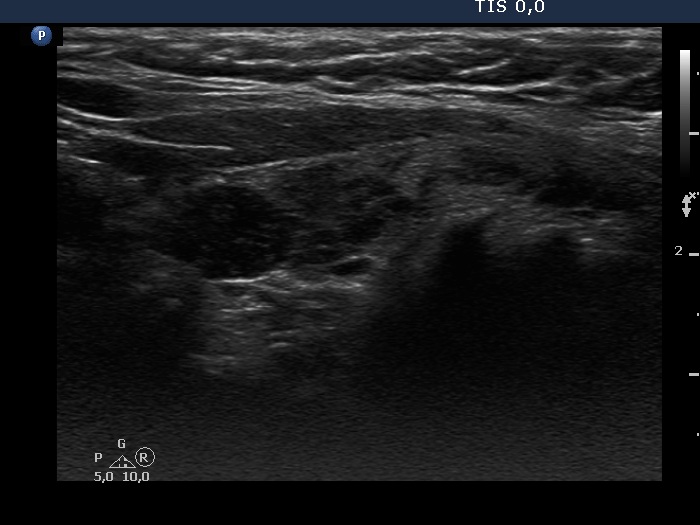

Discrete lesion or nodule in Hashimoto's thyroiditis - case 31 (1210) (ultrasonographic picture 5)

Left lobe, longitudinal view. The hypoechogenic lesion in the upper part (left in the image) is relatively well circumscribed.